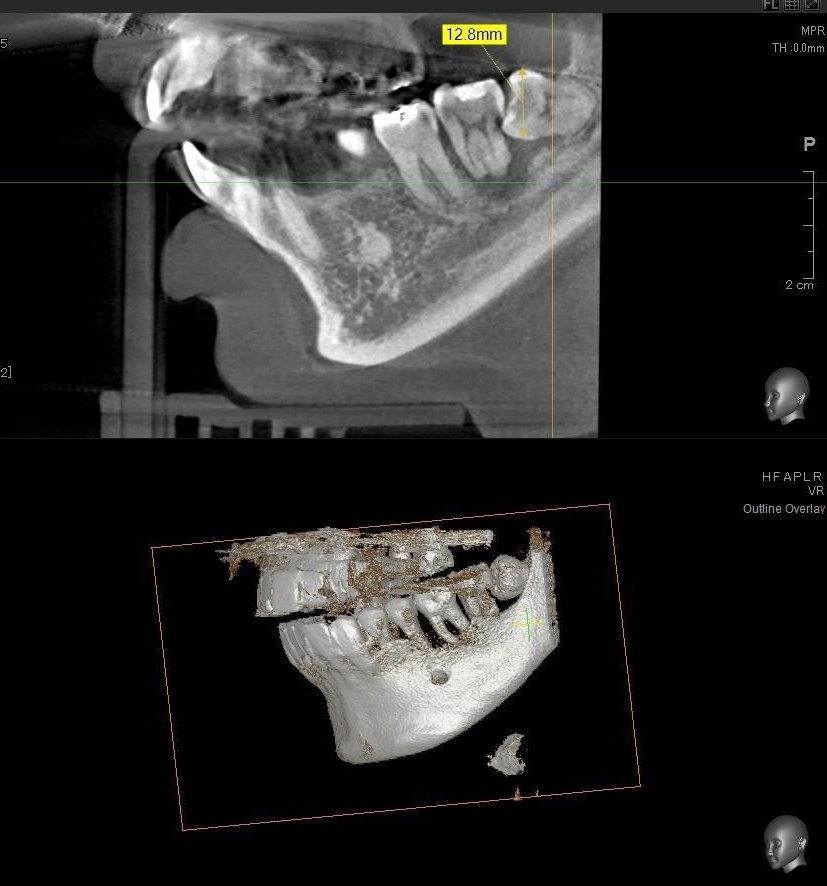

さらに、下顎の親知らずは下歯槽神経に非常に近いところに生えている場合もあるため、CTも撮影し詳しい解析を行います。

親知らずが生えている位置が、神経に近い、あるいは神経に当たっている場合は、大きな病院に紹介する場合もあります。

親知らずの根っこは下歯槽神経から近い距離にありますが、抜歯は可能との診断でした。